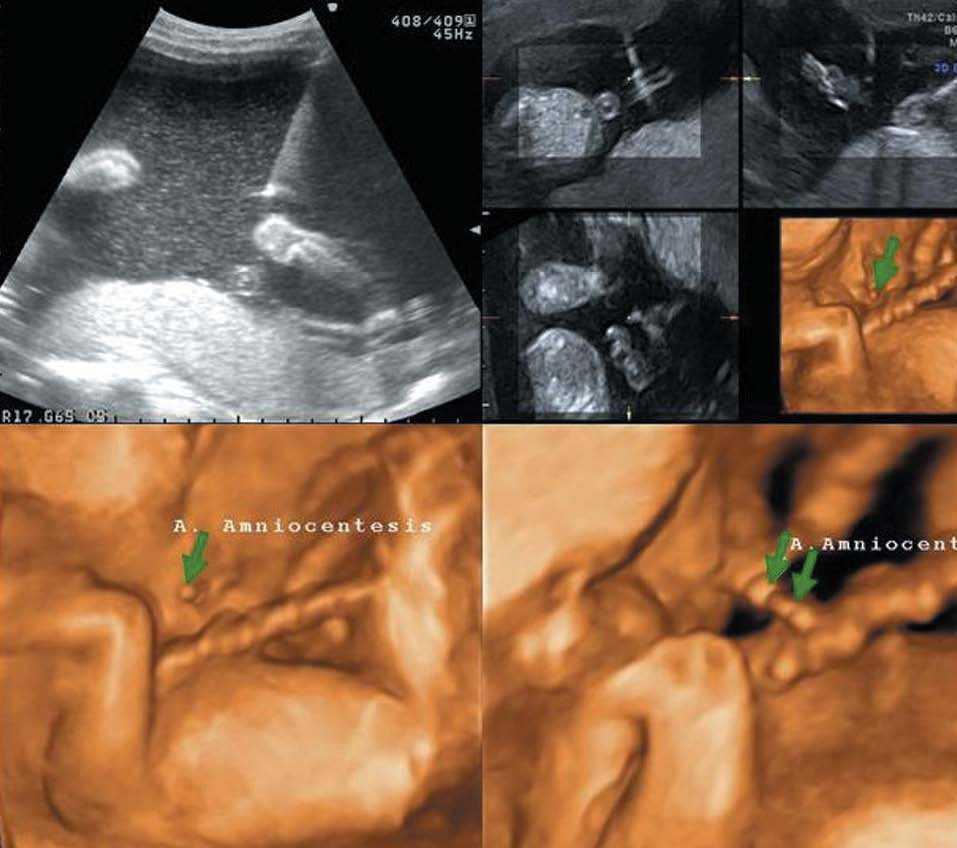

Técnicas invasivas

El modo 4D ha permitido mejorar las técnicas invasivas (amniocentesis, biopsia de vellosidades coriales, toracocentesis, cordocentesis y transfusión intrauterina), al lograr la visualización de la aguja en los 4 planos ortogonales y eliminar el fenómeno de lateralización14 (fig. 9).

Figura 9.Imagen 4D de una amniocentesis. Arriba) Planos ortogonales con la aguja entrando. Abajo (flechas verdes) La aguja ha penetrado en la cavidad y se aproxima al cordón para practicar la cordocentesis.